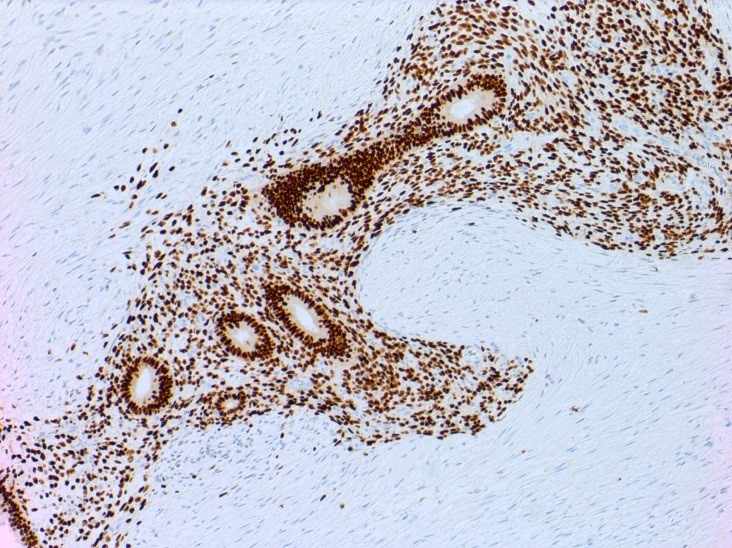

Microscopic (histologic) description

- At least 2 of the following 3 features

- Endometrial type glands

- Müllerian type epithelium (can be atrophic to cycling endometrium)

- Endometrial type stroma

- Often contains fine capillary network

Microscopic (histologic) images

Positive stains

- CD10 is positive in endometrial stroma

- ER, PR and PAX2 are often positive in endometrial glands and stroma (Am J Surg Pathol 2013;37:1342)